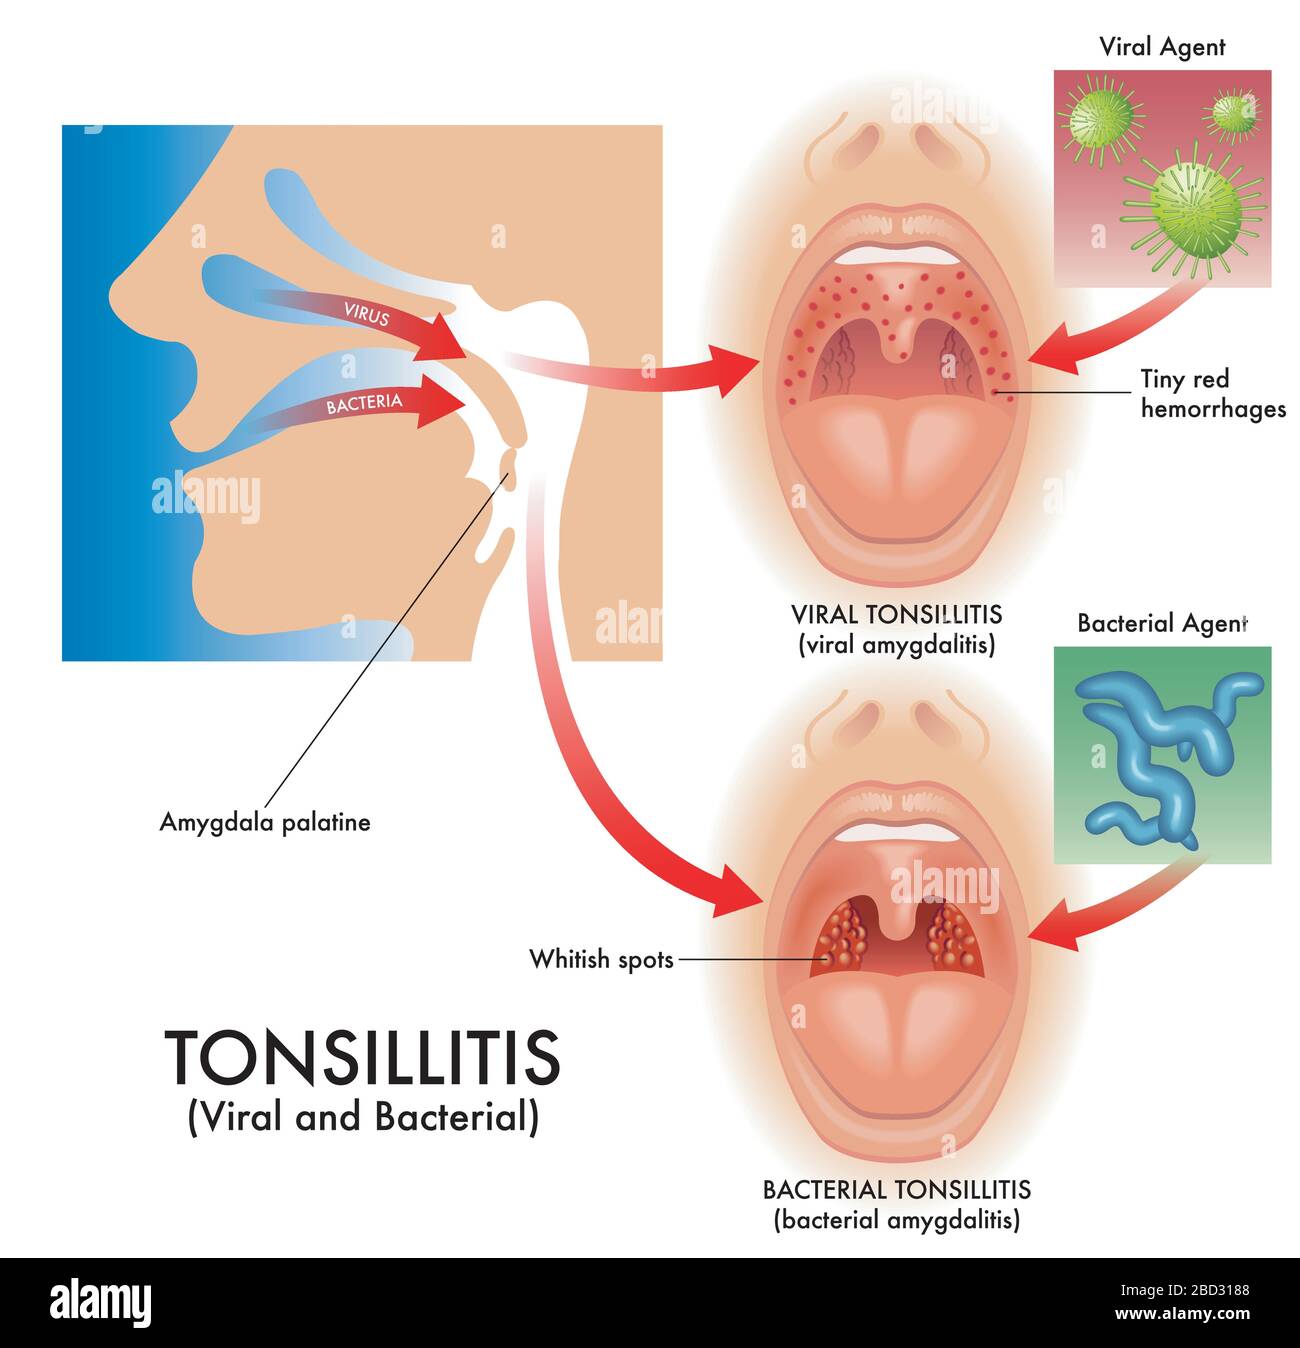

Medizinische Darstellung der Symptome einer viralen und bakteriellen Tonsillitis, auch virale Amygdalitis und bakterielle Amygdalitis genannt, mit den Erregern t Stock Vektorhttps://www.alamy.de/image-license-details/?v=1https://www.alamy.de/medizinische-darstellung-der-symptome-einer-viralen-und-bakteriellen-tonsillitis-auch-virale-amygdalitis-und-bakterielle-amygdalitis-genannt-mit-den-erregern-t-image352264760.html

Medizinische Darstellung der Symptome einer viralen und bakteriellen Tonsillitis, auch virale Amygdalitis und bakterielle Amygdalitis genannt, mit den Erregern t Stock Vektorhttps://www.alamy.de/image-license-details/?v=1https://www.alamy.de/medizinische-darstellung-der-symptome-einer-viralen-und-bakteriellen-tonsillitis-auch-virale-amygdalitis-und-bakterielle-amygdalitis-genannt-mit-den-erregern-t-image352264760.htmlRF2BD3188–Medizinische Darstellung der Symptome einer viralen und bakteriellen Tonsillitis, auch virale Amygdalitis und bakterielle Amygdalitis genannt, mit den Erregern t